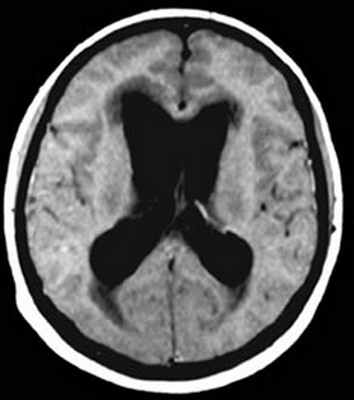

Увеличенные боковые желудочке на МРТ головного мозга при гидроцефалии с арахноидитом оболочек головного мозга.